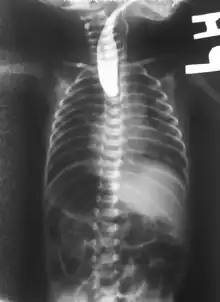

Diagnostic est post-natal

Juste après l'accouchement, deux types de tests peuvent être faits :

- une sonde « naso-gastrique » très fine peut être introduite dans l'œsophage du nouveau-né. Si elle est bloquée après quelques cm, c'est qu'il y a atrésie[3].

- test à la seringue

- l'IRM permet un diagnostic précis, mais est rarement utilisé chez les nouveau-nés[16]

Dans presque tous les cas une anomalie de la trachée est associée, et dans la moitié des cas environ[3], l'atrésie de l'œsophage est associée à d'autres malformations, comme dans le cadre du syndrome de VATER (présent dans 10 % des cas[3]) ou de VACTERL. Il convient donc de rapidement rechercher activement d'autres malformations associées qui peuvent toucher le cœur (dans 30 % des cas), mais aussi le squelette (25 % des cas), les reins, les membres, le système digestif (25 % des cas) ou urinaire[3].... Une échographie et une radiographie de l'abdomen confirme le type d'atrésie et des examens complémentaires portent notamment sur le cœur (échocardiographie) et l'anus (une sonde recherche une éventuelle perforation)[3].